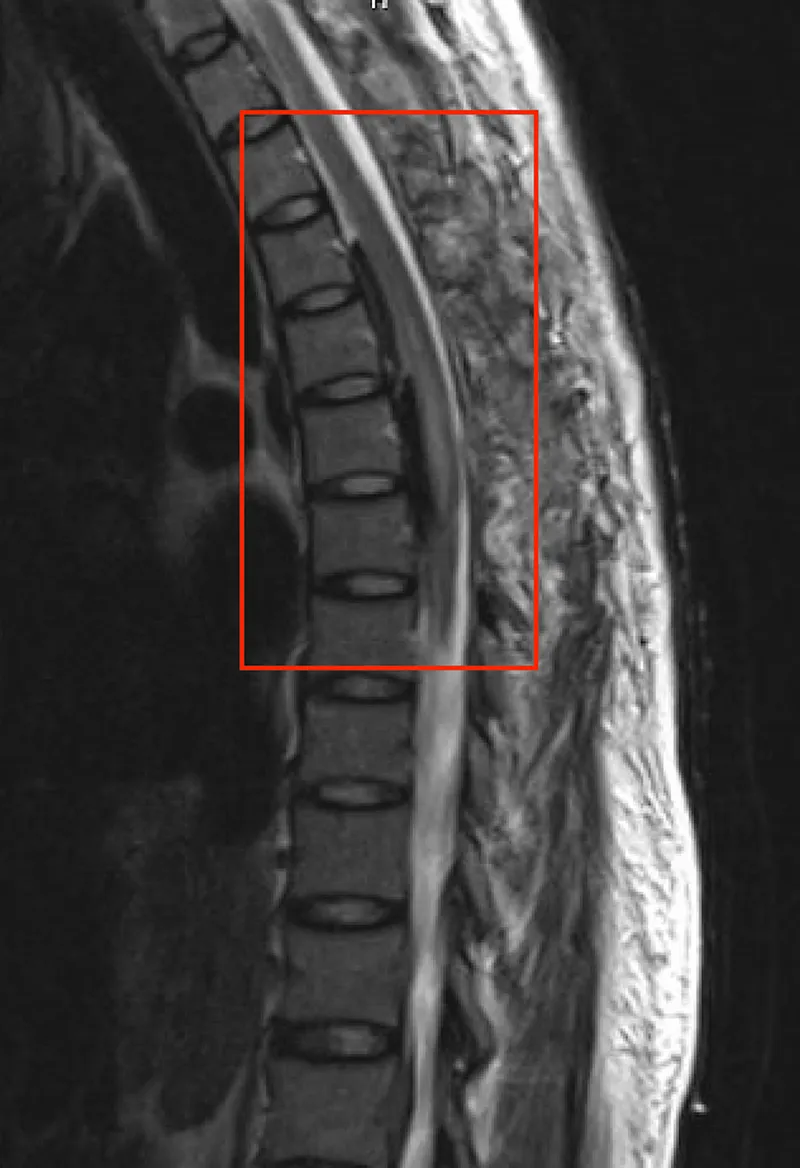

- Spinal/Epidural Hematoma: Neurological emergency!

- Symptoms: 📌 PAIN (Progressive deficit, Acute onset, Incontinence, Numbness), severe back/radicular pain, progressive motor/sensory deficits, bowel/bladder dysfunction.

- Dx: Urgent MRI.

- Rx: Neurosurgical consultation for decompressive laminectomy within 8-12 hours.

⭐ Spinal epidural hematoma is a neurological emergency requiring prompt diagnosis (MRI) and surgical decompression, ideally within 8-12 hours, to maximize chances of neurological recovery.